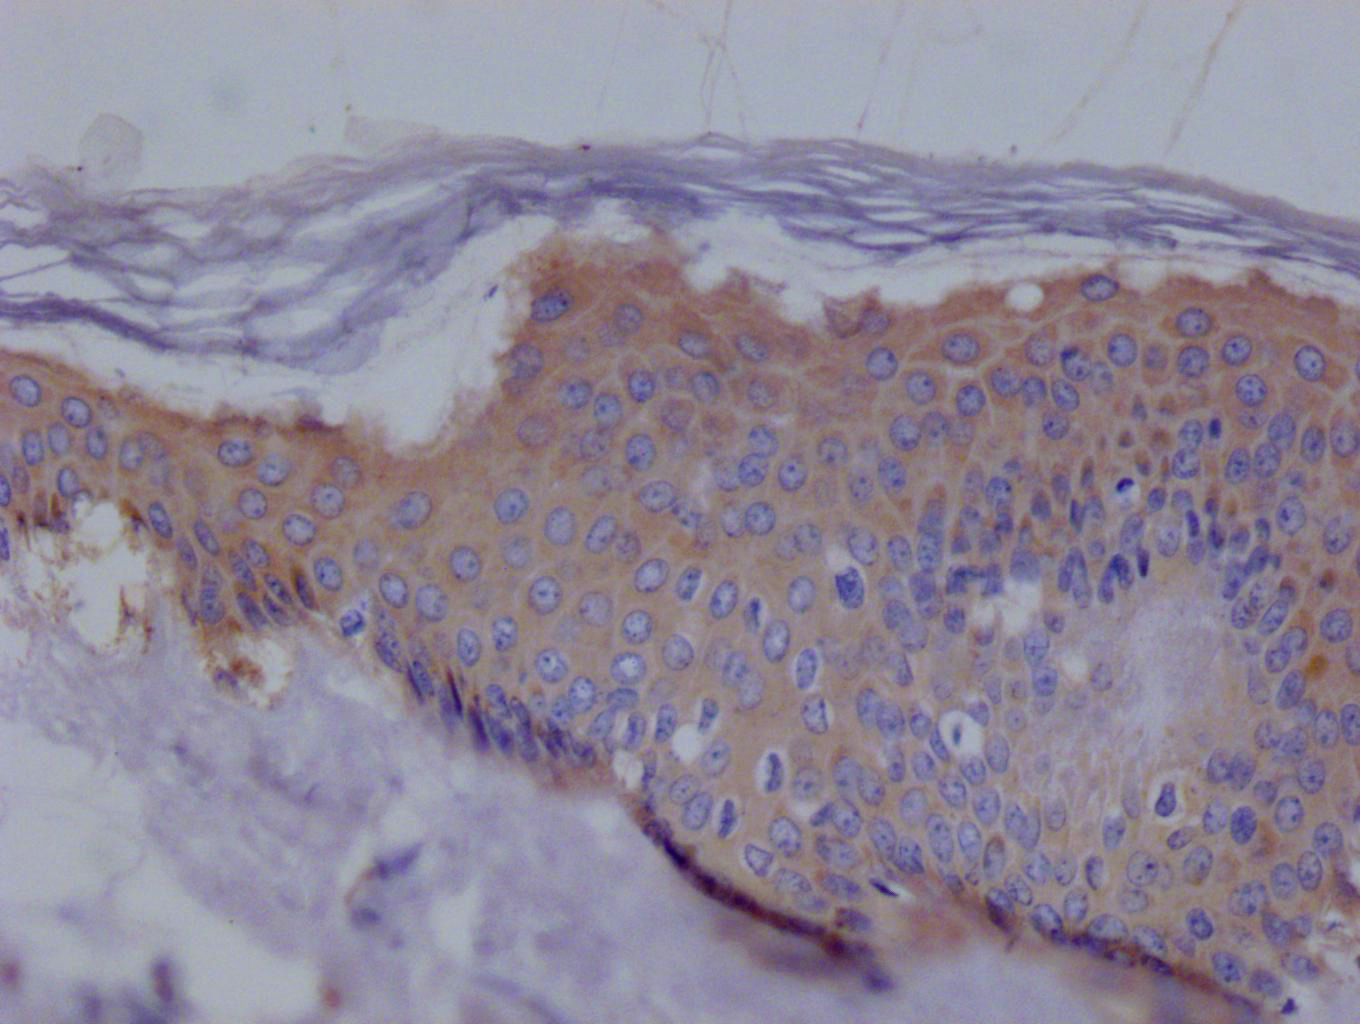

IHC image of CSB-RA194531A0HU diluted at 1:100 and staining in paraffin-embedded human skin tissue performed on a Leica BondTM system. After dewaxing and hydration, antigen retrieval was mediated by high pressure in a citrate buffer (pH 6.0). Section was blocked with 10% normal goat serum 30min at RT. Then primary antibody (1% BSA) was incubated at 4°C overnight. The primary is detected by a Goat anti-rabbit polymer IgG labeled by HRP and visualized using 0.05% DAB.